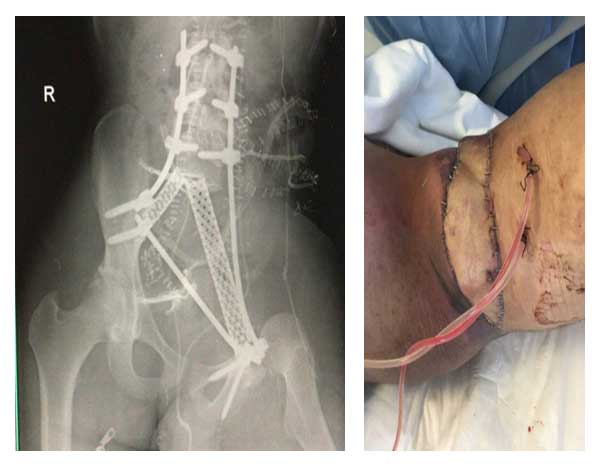

Ameliyat Sonrası: Röntgende lumbopelvik fiksasyon ve cage ile rekonstrüksiyon sonrası yaranın kapatılması görülmekte.

24 yaşındaki erkek hastada sakrum ve iliak kanat yerleşimli osteosarkom tanısı sonrası kemoterapi uygulanmıştır. Metastaz saptanmayan hastaya total sakrektomi ve hemipelvektomi sonrası lumbopelvik fiksasyon ve cage ile rekonstrüksiyon işlemi yapılmıştır. Yara kapatılması karın ön duvarından kaslı flep (VRAM) çevrilerek gerçekleştirilmiştir.

• Hastaya total sakrektomi ve hemipelvektomi sonrası lumbopelvik fiksasyon ve cage ile rekonstrüksiyon işlemi uygulanmıştır.

• Karın ön duvarından kaslı flep (VRAM) çevrilerek yara kapatılmıştır.